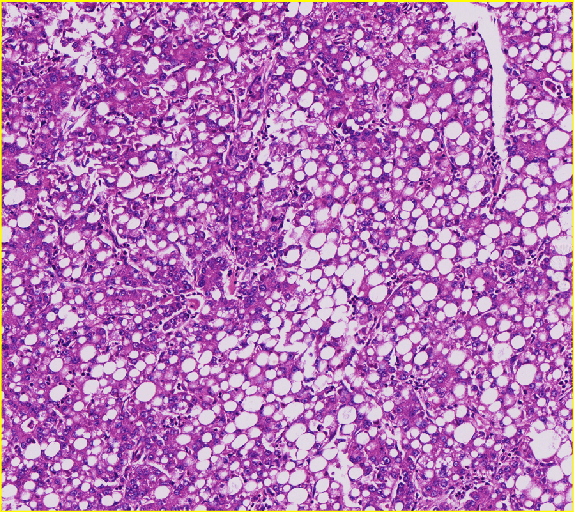

脂肪空泡分析